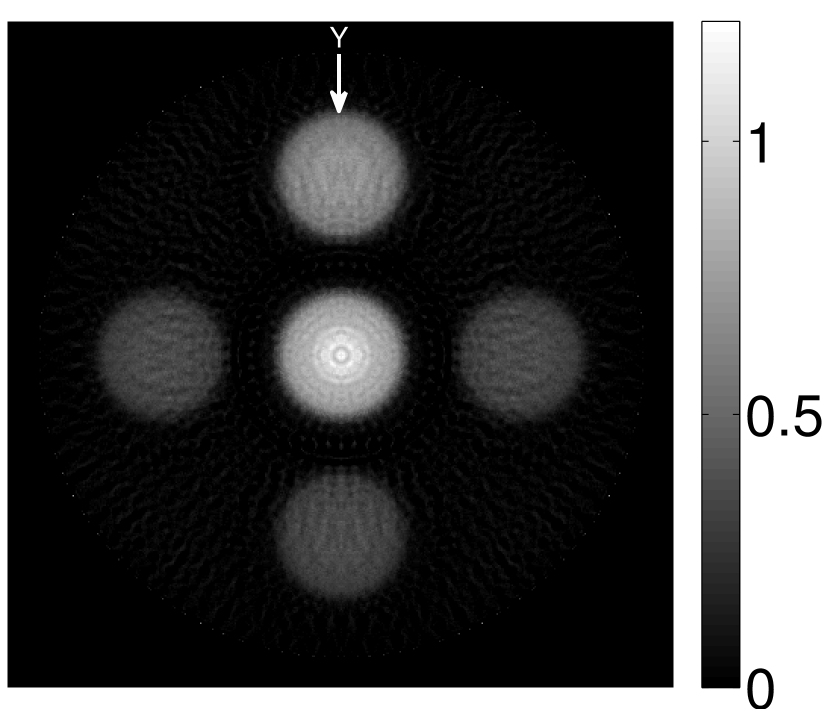

V-A3 Effect of data incompleteness

Incomplete, or sparsely sampled, data sets are sometimes acquired in practice. To study the effect of data incompleteness on the VP algorithm, we reconstructed images from data corresponding to half of the equally spaced transducers (). Because the data were noiseless, no explicit regularization was employed () in the conventional reconstruction algorithm. However, the explicit regularization was still employed in the VP algorithm because of the ill-posed nature of the joint reconstruction problem. The results are shown in Figure 5. As expected, use of the incomplete data set resulted in less accurate reconstructed images for both the conventional iterative reconstruction method and the VP algorithm. However, this effect was more pronounced for the VP algorithm. Note that for the VP algorithm, larger values of the regularization parameters were applied when the incomplete data set was employed than when the complete data set was employed (Figure 5(h) and 5(g)).